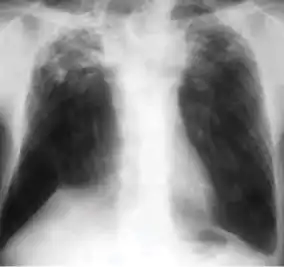

In active pulmonary TB, infiltrates or consolidations and/or cavities are often seen in the upper lungs with or without mediastinal or hilar lymphadenopathy.[1] However, lesions may appear anywhere in the lungs. In HIV and other immunosuppressed persons, any abnormality may indicate TB or the chest X-ray may even appear entirely normal.[1]

Old healed tuberculosis usually presents as pulmonary nodules in the hilar area or upper lobes, with or without fibrotic scars and volume loss.[1] Bronchiectasis and pleural scarring may be present.

Nodules and fibrotic scars may contain slowly multiplying tubercle bacilli with the potential for future progression to active tuberculosis.[1] Persons with these findings, if they have a positive tuberculin skin test reaction, should be considered high-priority candidates for treatment of latent infection regardless of age. Conversely, calcified nodular lesions (calcified granuloma) pose a very low risk for future progression to active tuberculosis.

Abnormalities on chest radiographs may be suggestive of, but are never diagnostic of, TB.[1] However, if a person has a positive response to the tuberculin skin test and no symptoms of the disease, chest radiographs can be used to rule out the possibility of pulmonary TB.